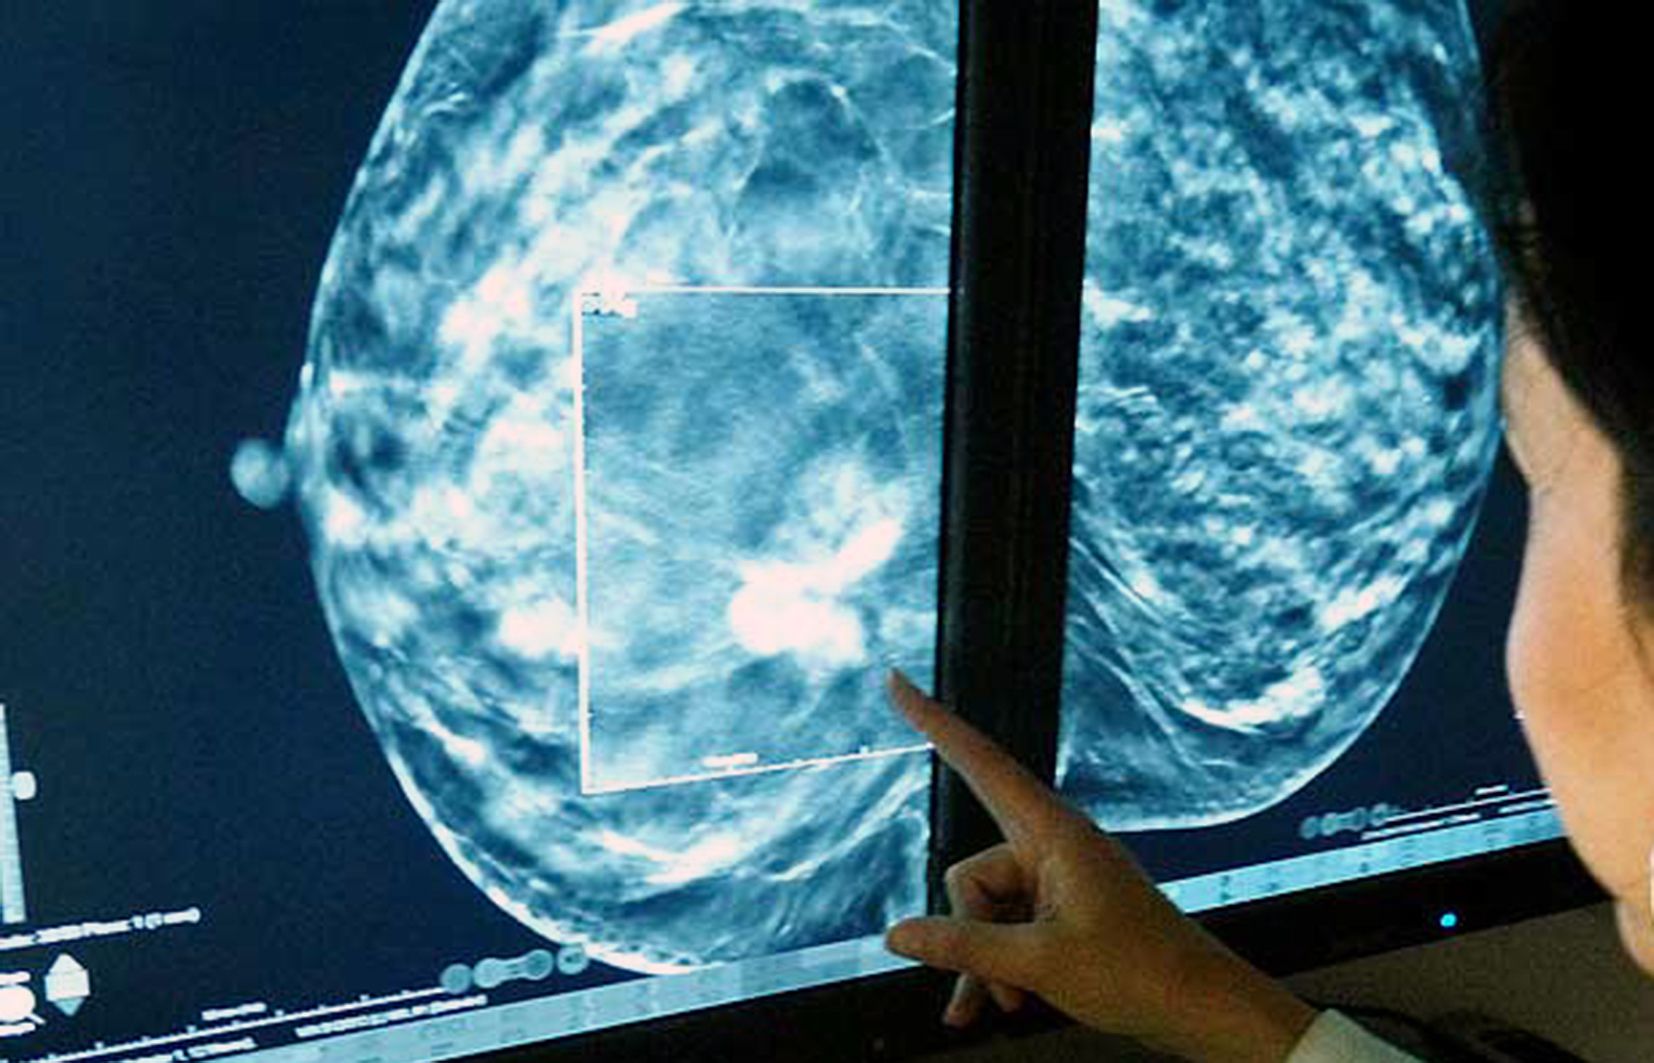

“El nostre objectiu és acompanyar a les persones i estar al seu costat, trobar els tractaments més adequats”, ha puntualitzat Benazet. De moment, també ha posat sobre la taula els resultats del programa de detecció de càncer de mama, on des del gener de 2020, quan es va ampliar l’edat fins als 74 anys, s’han detectat 28 casos. I ha mantingut la posició en aquesta línia, “buscant implementar les peces que ens ajudaran a un diagnòstic ràpid”, i que amb el nou equip “es prendran millors decisions”. Per tant, el reclam del president de l’Associació Contra el Càncer, Josep Maria Saravia, de moment, cau en sac buit. “No sempre el confort equival a la millor solució per a la salut de la persona”, ha sentenciat el ministre.